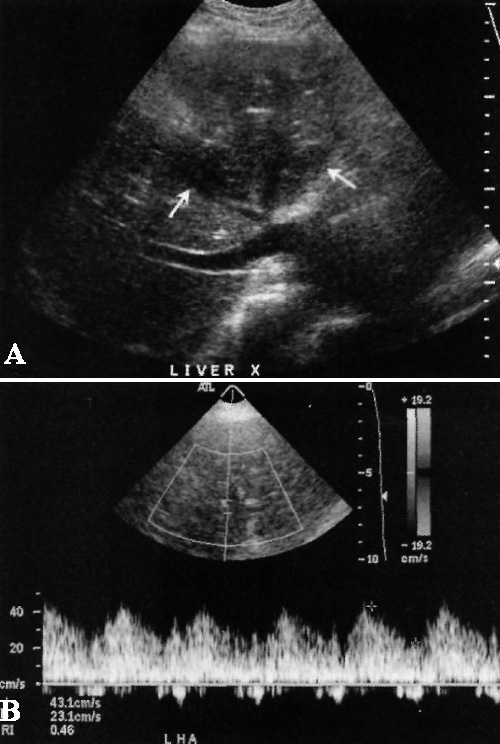

Сочетание показателя индекса резистентности < 0,05 и времени ускорения > 0,08 с примерно в 73-81% случаев свидетельствует о стенозе печеночной артерии (фото 1).

Фото 1. Инфаркт печени. А – стрелками обозначен тромбоз печеночной артерии с инфарктом левой доли печени. В – левая печеночная артерия с пульсовой кривой, которая соответствует низкому сопротивлению кровотока (показатель индекса резистентности < 0,05). Отметим, что такая картина может свидетельствовать как о стенозе печеночной артерии, так и о коллатеральной перфузии, которая возникает в ответ на тромбоз печеночной артерии